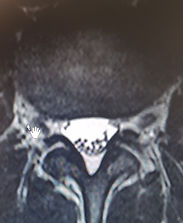

mri showing a slipped disc

This scan shows older discs that are less well hydrated and thus appear black. The highlighted area shows that a disc has herniated or slipped into the spinal canal. This is likely to be associated with a great deal of pain in the back and leg